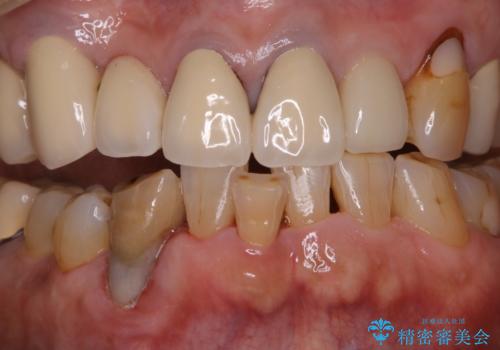

半年ぶりのクリーニング PMTC

- 半年、来院できなかったためきれいにクリーニングしたいとのことでした。久しぶりだったことと、全体的に汚れが付着していたためPMTC60分コースを行いました。